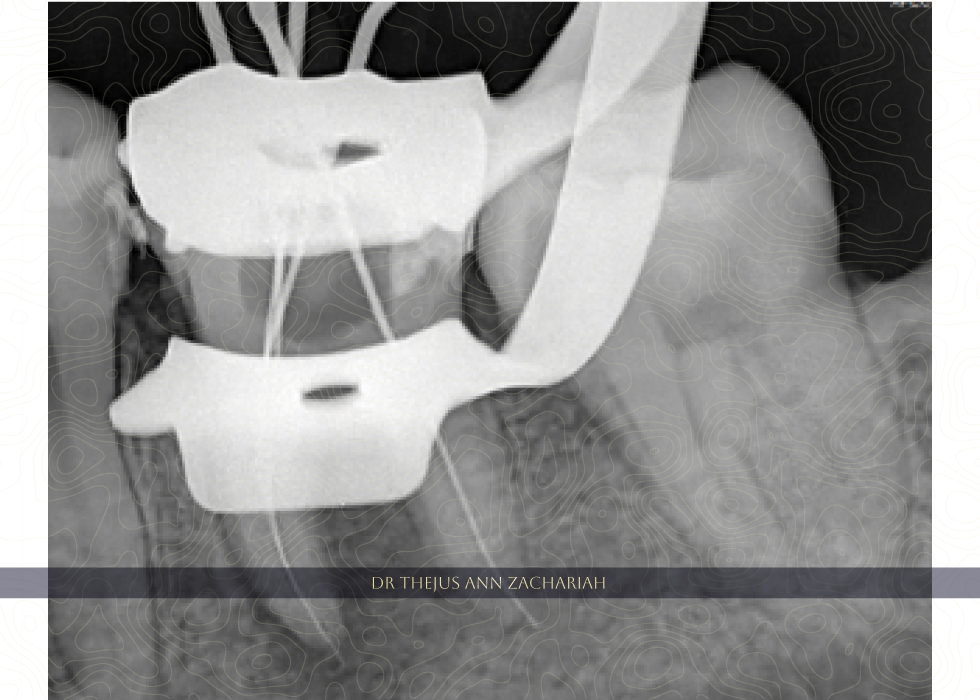

Access Opening Through Crown

Working Length